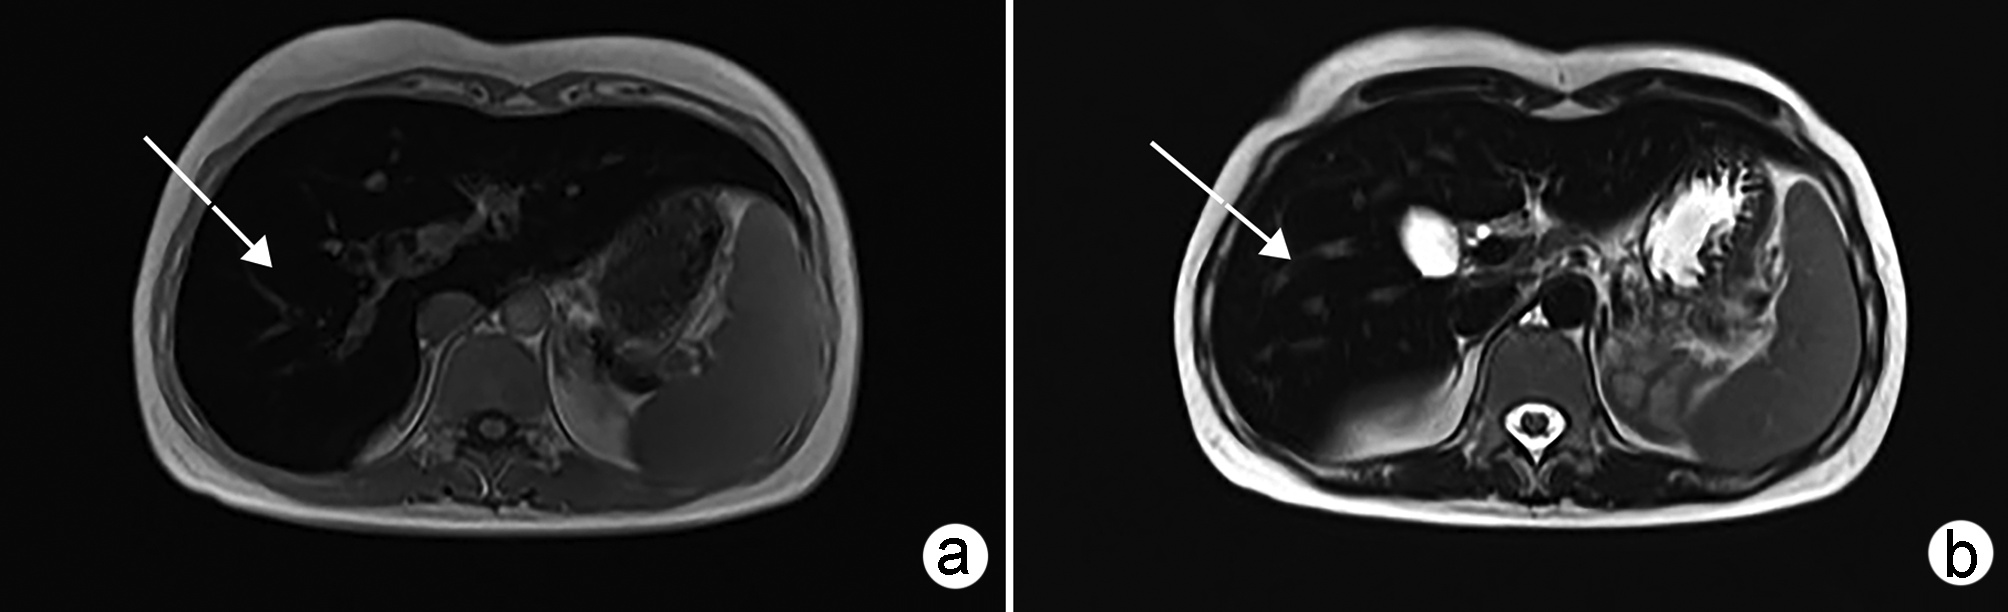

Construction and validation of a nomogram model for microvascular invasion in hepatocellular carcinoma based on the characteristics on contrast-enhanced ultrasound Liver Imaging Reporting and Data System

Jing XI, Meiqin GU, Zuowei BAO

2022, 38(11): 2520-2525. DOI: 10.3969/j.issn.1001-5256.2022.11.016

Abstract(849) HTML (325) PDF (2938KB)(46)

Abstract:

Objective  To construct and validate a nomogram model for predicting microvascular invasion (MVI) based on the characteristics on contrast-enhanced ultrasound (CEUS) Liver Imaging Reporting and Data System (LI-RADS) in patients with hepatocellular carcinoma (HCC).  Methods  A total of 262 patients with HCC who were diagnosed in Wujin Hospital Affiliated to Jiangsu University from January 2017 to July 2020 were enrolled and randomly divided into modeling group and validation group at a ratio of 1∶ 1, with 131 patients in each group. MVI was confirmed by postoperative microscopic pathological results, and there were 70 patients with MVI in the modeling group and 56 patients with MVI in the validation group. CEUS was used to evaluate LI-RADS characteristics for the two groups. The independent samples t-test was used for comparison of continuous data between the two groups, and the chi-square test was used for comparison of categorical data between the two groups. Univariate and multivariate Logistic regression analyses were used to identify the risk factors for MVI in the modeling group; the receiver operating characteristic (ROC) curve was plotted, and the area under the ROC curve (AUC) was calculated for the model in predicting MVI to evaluate the accuracy of prediction; a decision curve analysis was used to evaluate the consistency of the model, and dispersion was compared between the calibration curve and the standard curve for the model in predicting MVI.  Results  There were no significant differences in clinical data and CEUS findings between the modeling group and the validation group (all P > 0.05). The univariate analysis showed that compared with the MVI-negative patients, the MVI-positive patients had significant increases in serum alpha fetoprotein (AFP) level, tumor diameter, and LR-5 "late and mild washout" and LR-M "early washout" on LI-RADS, as well as a significantly higher LI-RADS grade (all P < 0.05). The multivariate analysis showed that AFP 20-400 ng/mL (odds ratio [OR]=2.65, P < 0.001), AFP≥400 ng/mL (OR=3.98, P < 0.001), tumor diameter ≥30 mm (OR=2.12, P < 0.001), and LR-M on CEUS (OR=3.24, P < 0.001) were independent risk factors for MVI. The ROC curve analysis showed that the nomogram had an AUC of 0.867 and 0.821 in predicting MVI in the modeling group and the validation group, respectively. The nomogram model had a C-Index of 0.765 (95% confidence interval: 0.701-0.834). The calibration curves of the nomogram model were close to the standard curve in both groups.  Conclusion  The nomogram model based on LI-RADS obtained by CEUS in combination with AFP and tumor diameter has a good application value and can guide the preoperative screening for patients at a high risk of MVI and the development of appropriate surgical plans in clinical practice.